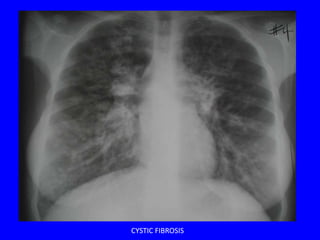

CYSTIC FIBROSIS

• Diffuse bronchiectasis

• Most severe in the upper lobes

Worse in the

upper lung

zones